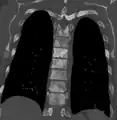

Osteosclerosis is a disorder characterized by abnormal hardening of bone and an elevation in bone density. It may predominantly affect the medullary portion and/or cortex of bone. Plain radiographs are a valuable tool for detecting and classifying osteosclerotic disorders.[1][2] It can manifest in localized or generalized osteosclerosis. Localized osteosclerosis can be caused by Legg–Calvé–Perthes disease, sickle-cell disease and osteoarthritis among others. Osteosclerosis can be classified in accordance with the causative factor into acquired and hereditary.[2][1]

Osteosclerosis can be detected with a simple radiography. There are white portions of the bone which appear due to the increased number of bone trabeculae.